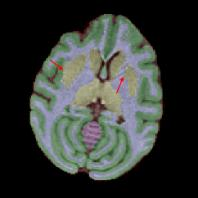

Non-human primates (NHPs) serve as critical models for understanding human brain function and neurological disorders due to their close evolutionary relationship with humans. Accurate brain tissue segmentation in NHPs is critical for understanding neurological disorders, but challenging due to the scarcity of annotated NHP brain MRI datasets, the small size of the NHP brain, the limited resolution of available imaging data and the anatomical differences between human and NHP brains. To address these challenges, we propose a novel approach utilizing STU-Net with transfer learning to leverage knowledge transferred from human brain MRI data to enhance segmentation accuracy in the NHP brain MRI, particularly when training data is limited. The combination of STU-Net and transfer learning effectively delineates complex tissue boundaries and captures fine anatomical details specific to NHP brains. Notably, our method demonstrated improvement in segmenting small subcortical structures such as putamen and thalamus that are challenging to resolve with limited spatial resolution and tissue contrast, and achieved DSC of over 0.88, IoU over 0.8 and HD95 under 7. This study introduces a robust method for multi-class brain tissue segmentation in NHPs, potentially accelerating research in evolutionary neuroscience and preclinical studies of neurological disorders relevant to human health.